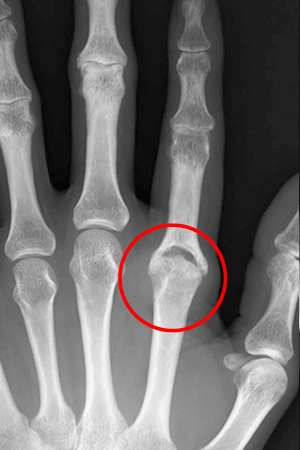

症例1

135歳女性の患者さん、人差し指の第3関節(MP関節)に炎症を起こし腫れていました。

2ステロイド関節内注射により腫れは引きましたが、痛みが持続するためMRIを撮ってみると、滑膜の炎症が残っていました。

3そのため手術をして滑膜除去を行ったところ、スッキリしネイルアートも楽しめるようになりました。